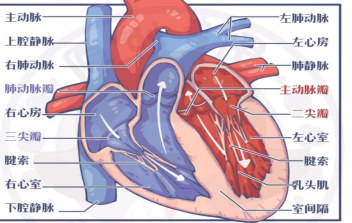

胎儿心室强光斑,也叫心内强回声光点(EIF),是在超声检查时胎儿心室内出现的、与邻近肋骨回声相似或者更强的超声现象,可单发或多发,左心室多见。

我们的心脏,由好几个房间组成,左右各有一个心房和心室,两侧的心房和心室之间,都有一扇门隔开。

控制这两扇门打开、关闭的,是一些像锁链一样的组织,一头连在墙上,一头连在门上。如果这些锁链增粗、增多,或者因为胎儿心脏太小,锁链和门分不太清楚,那么B超下就会看到强光斑。